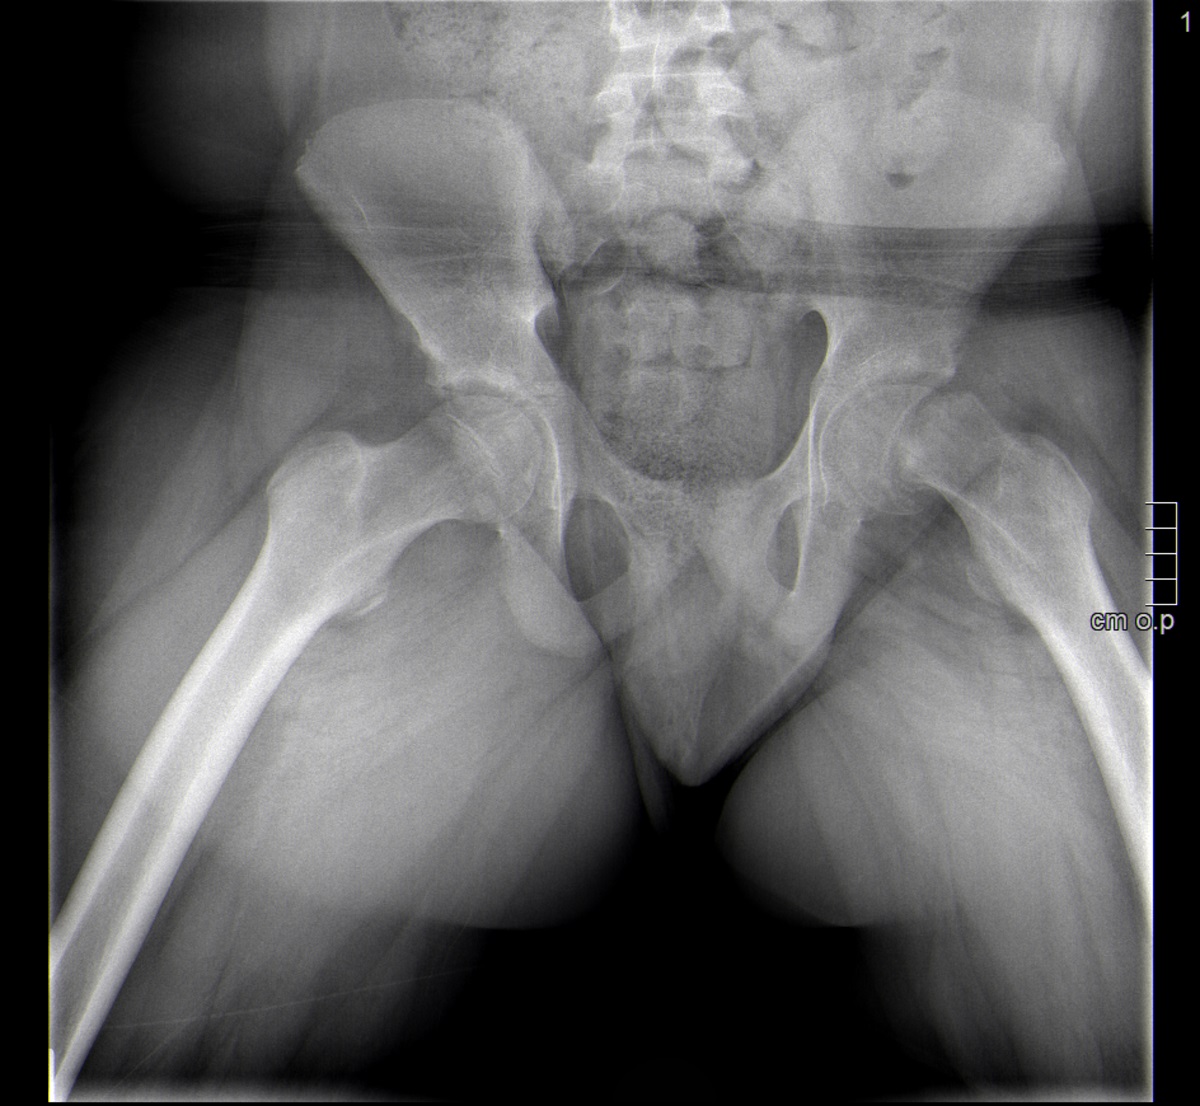

Paciente de 13 años que consulta por una dudosa sensación de disnea. Afebril, sin clínica de enfermedades infecciosas. A la exploración destaca obesidad y ausencia de signos de distrés respiratorio, con auscultación cardiopulmonar normal. Llama la atención una marcha antiálgica del paciente, que precisa la ayuda de muletas. Por anamnesis dirigida refiere gonalgia izquierda de mes y medio de evolución coincidente con un papiloma en el pie contralateral. En la exploración de los miembros inferiores presenta una marcada limitación a la rotación interna y la flexión de la cadera izquierda, con exploración de la rodilla normal. Se realiza radiografía de pelvis en proyección anteroposterior (Figura 1) y oblicua (Figura 2).

Figura 2. Radiografía de pelvis en proyección oblicua.